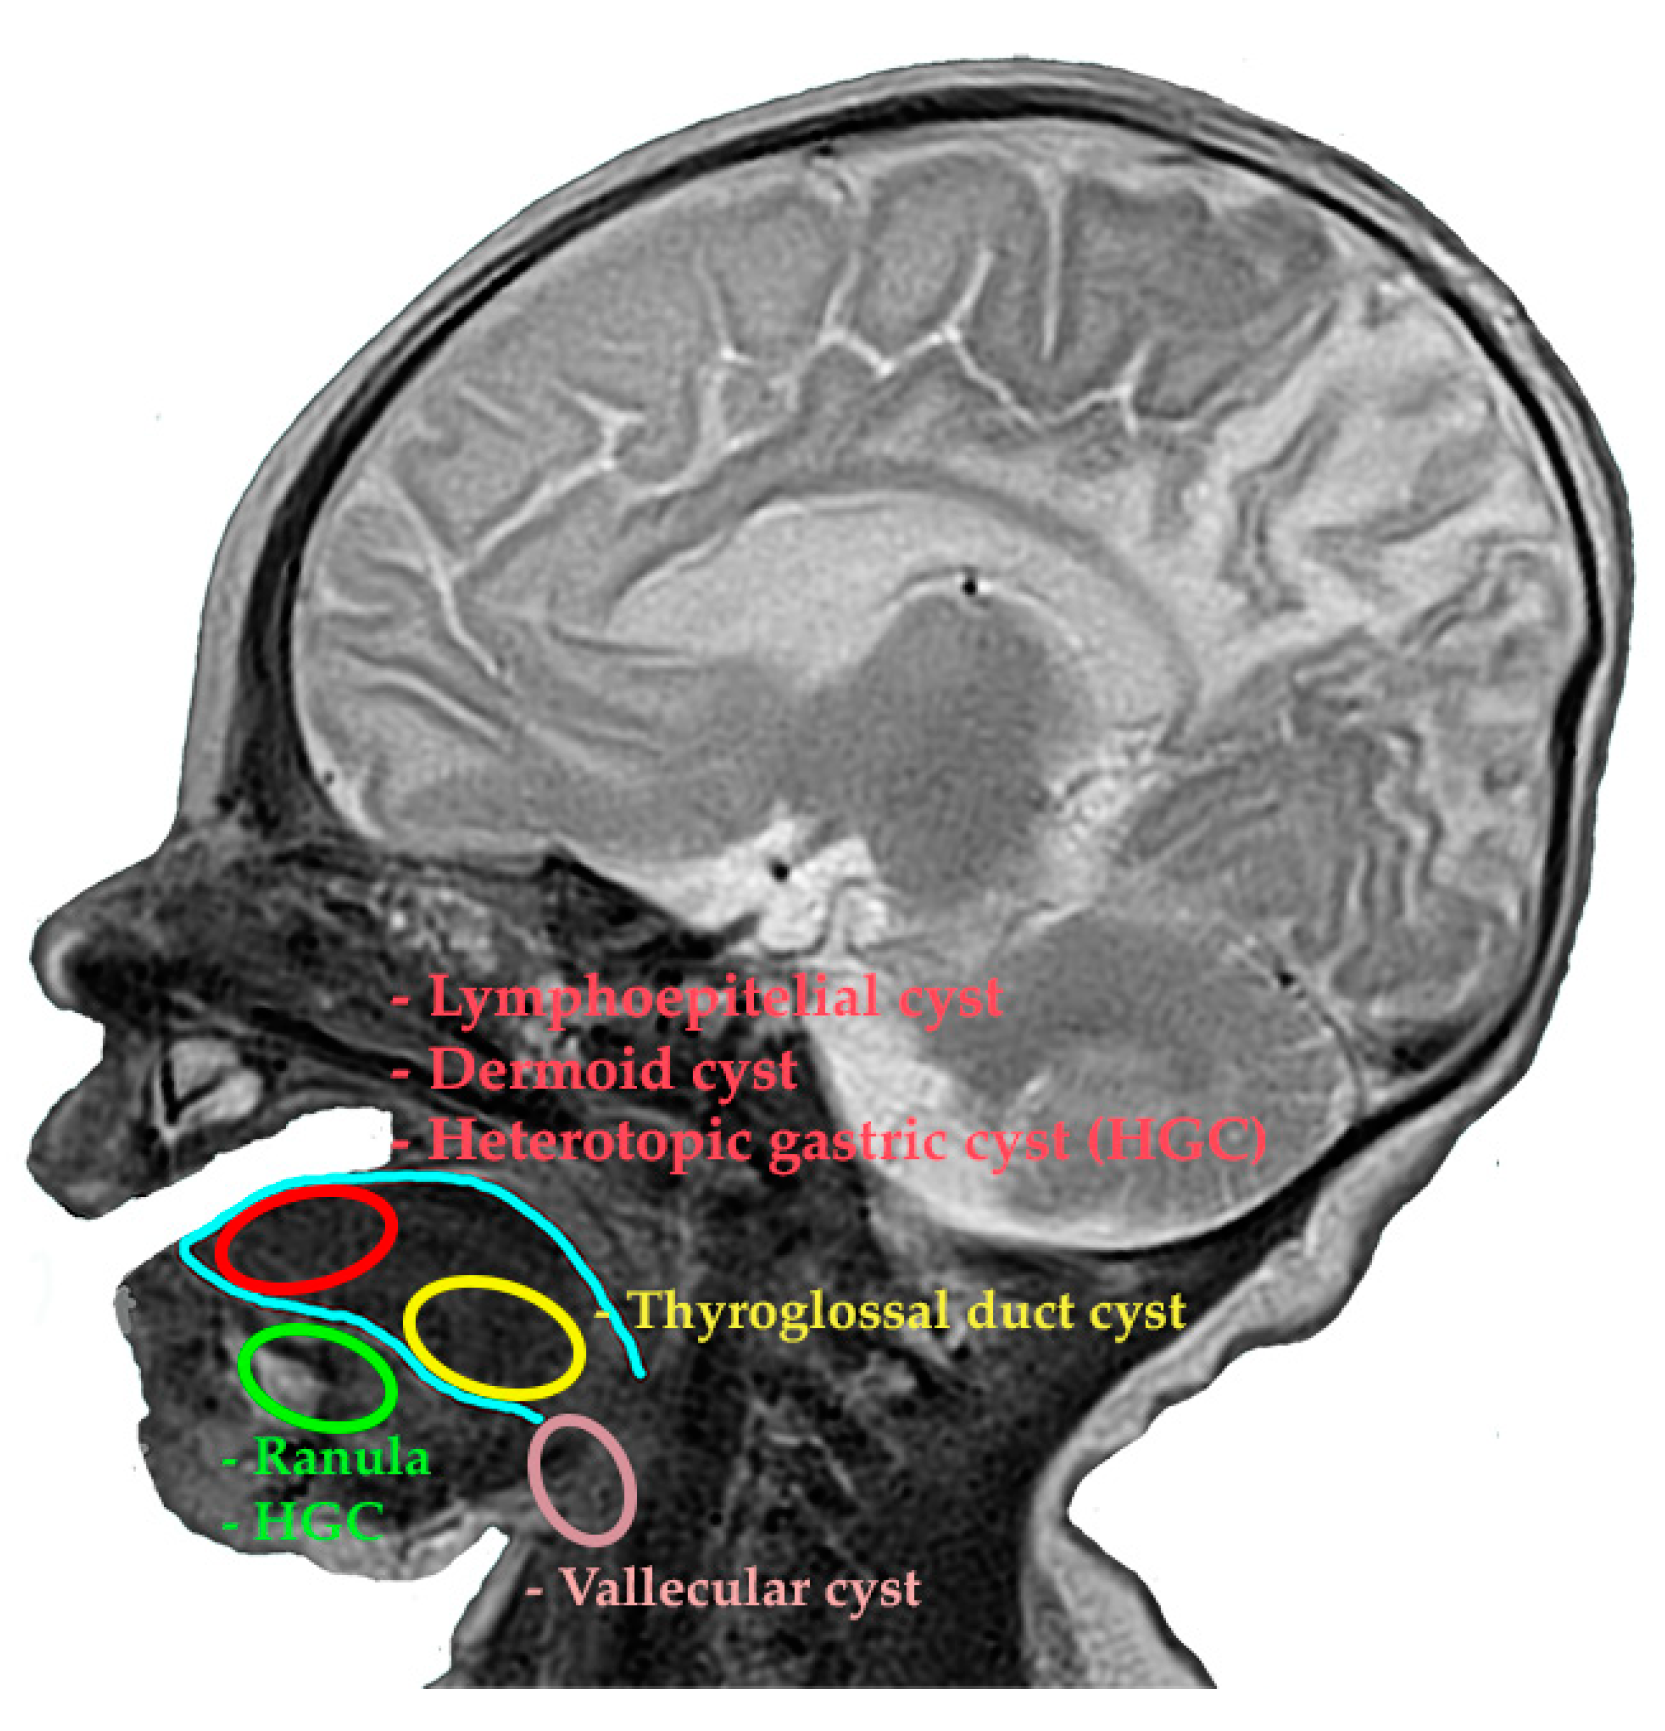

The differential diagnosis of cystic formations is carried out from a topographical and mainly histological point of view. Thus, a cyst located anteriorly, posteriorly, or on the floor of the mouth in the fetus may include the following diagnoses: ranula, a thyroglossal duct cyst, lymphoepithelial cyst, dysontogenetic cyst (dermoid cyst), heterotopic gastrointestinal and/or respiratory cyst, vallecular cyst, and hemangioma [5,6] (Figure 4).

Figure 4. The main sites of lingual cystic formations using an MRI reconstruction.